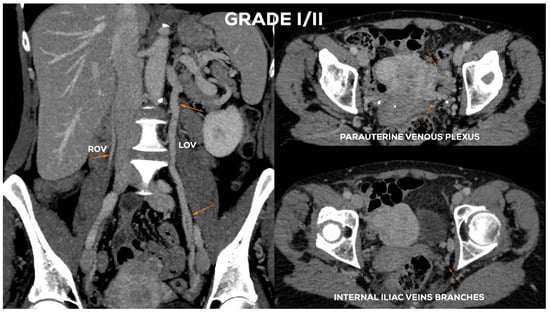

4.2.2. Grade I/II (GI/II)

| GI/II | 6–6.5 | (+) | <5.5 | <5.5 | <5 | (−) | <5 | <5 |